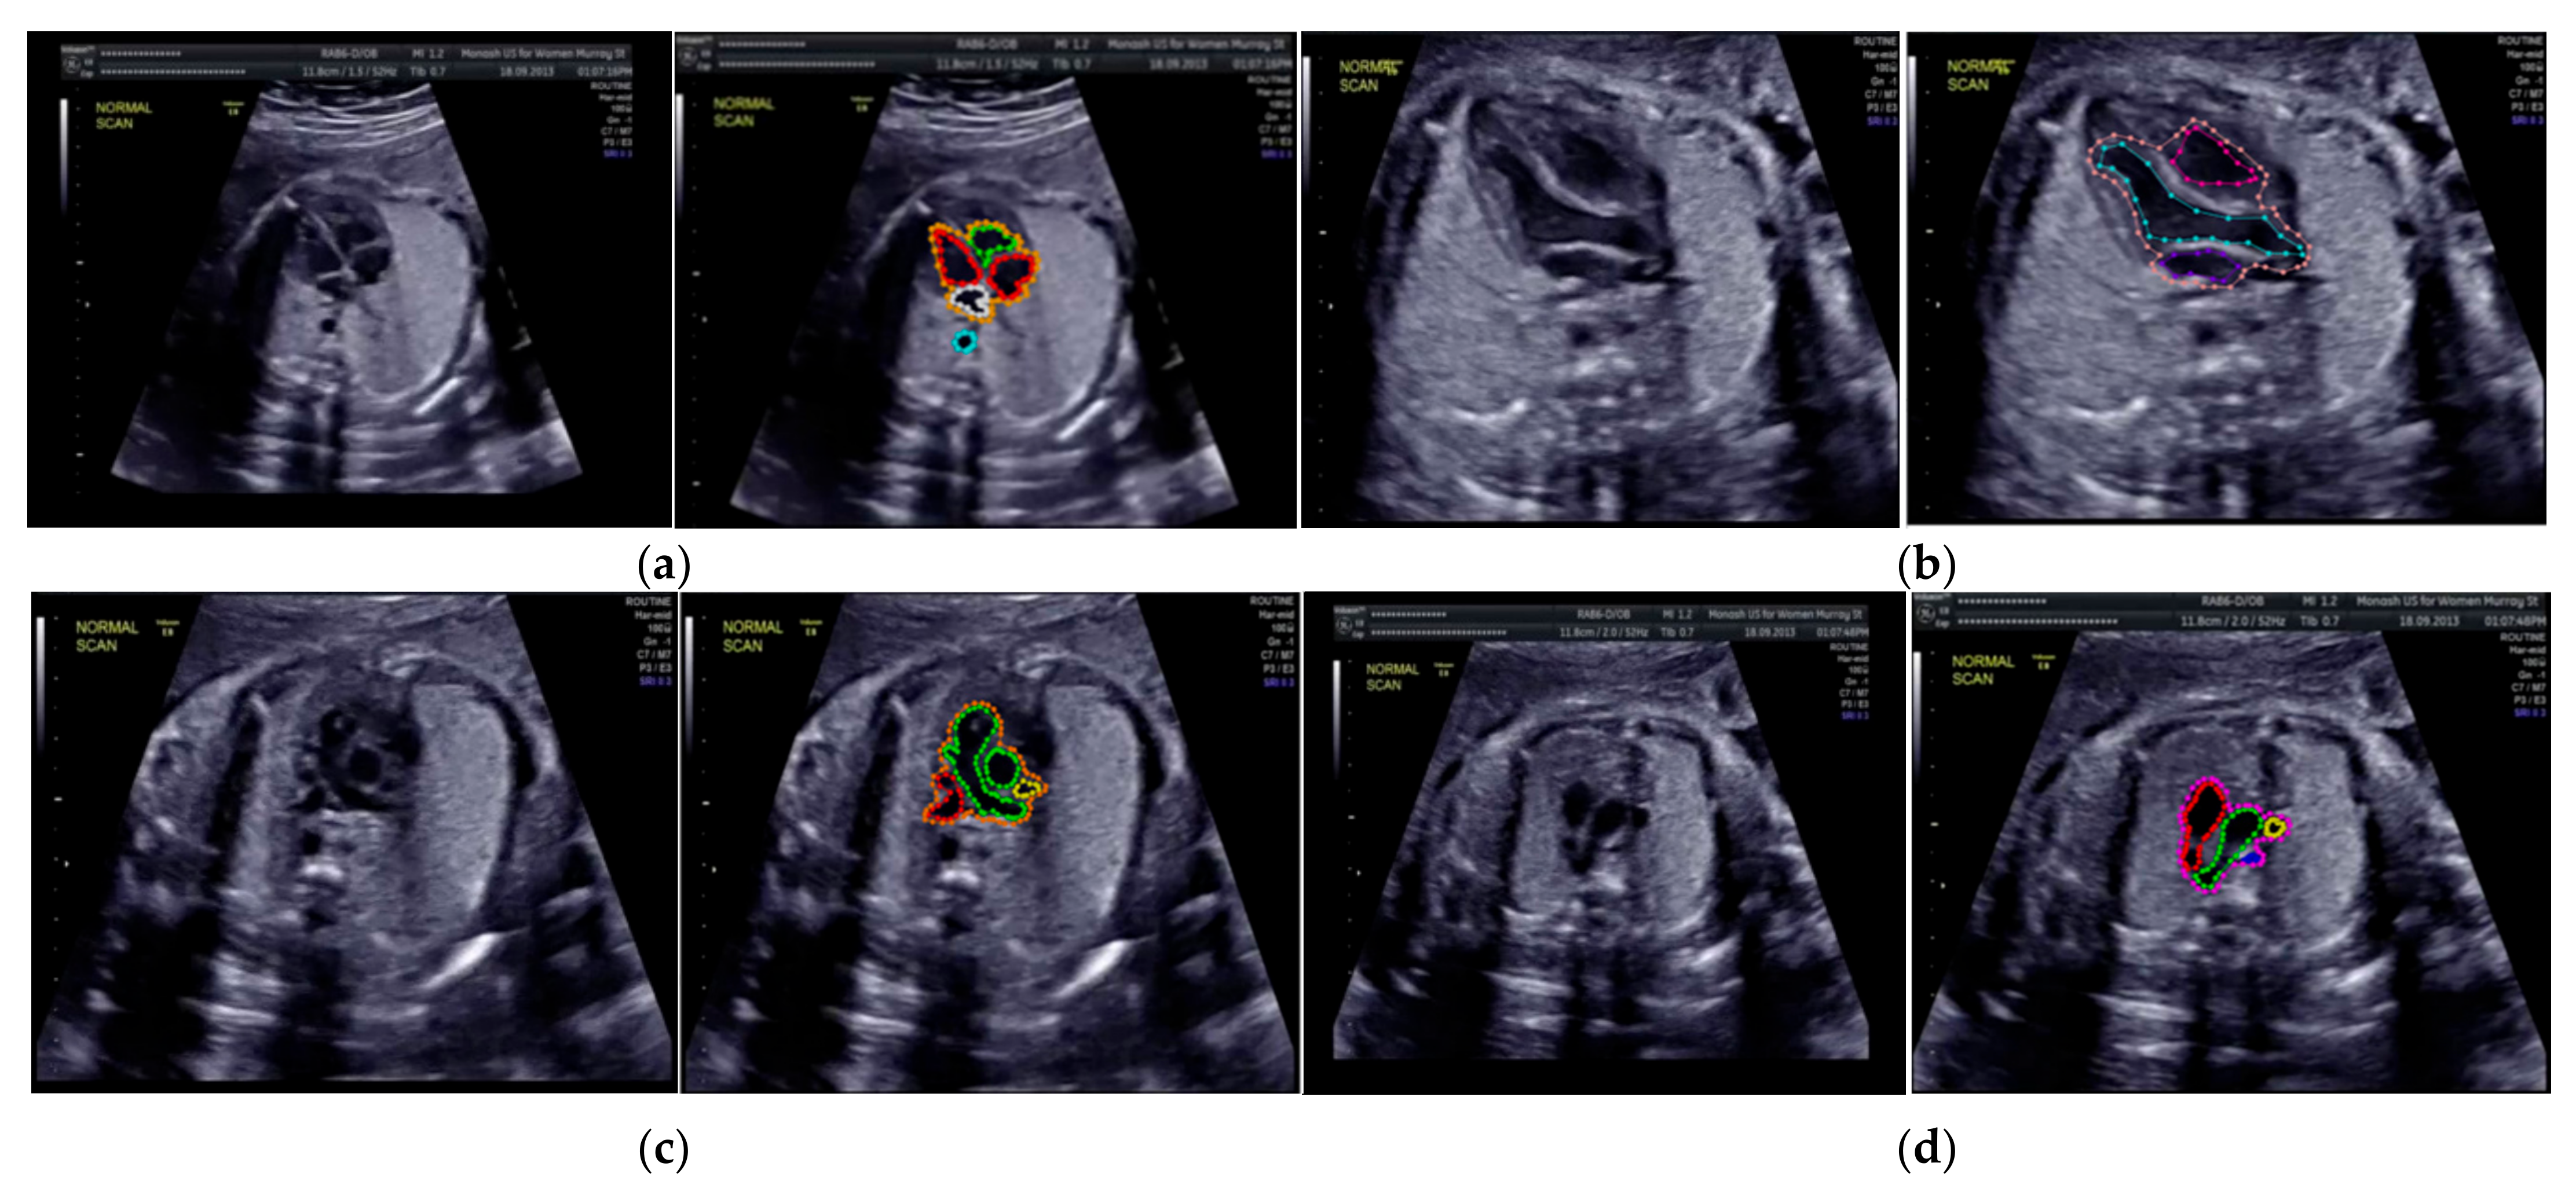

Especially for heart defect detection, only 4CH view was used to analyze ASD, VSD, and AVSD images. Annotated images indicate the position of defect in the atrium, ventricle, or both of them. Figure 4 depicts the sample of annotated images for a standard view of 4CH, 3VT, LVOT, and RVOT, and Figure 5 shows the sample annotated images of defect position in ASD, VSD, and AVSD. Finally, the whole annotated images are labelled as the ground truth database, and it was saved in the JSON file format (json).

Figure 4.

The sample of annotated images by maternal–fetal clinician for standard fetal heart view segmentation in (a) 4CH (orange: view, cyan: AoA, red: LA, grey: RA, green: LV, and red: RV); (b) LVOT (orange: view, cyan: LA, purple: RV, and blue: LV); (c) RVOT (orange: view, green: MPA, red: DUCT, and yellow: SVC); and (d) 3VT (purple: view, yellow: AoA, green: SVC, and red: DUCT); based on normal anatomy.

Figure 5.

The sample of annotated image by maternal–fetal clinician for heart defect detection in case: (a) ASD; (b) VSD; and (c) AVSD. In the annotation, the green line is RA, the red line is LA, the purple line is RV, the blue line is LV, and the yellow line is defect.